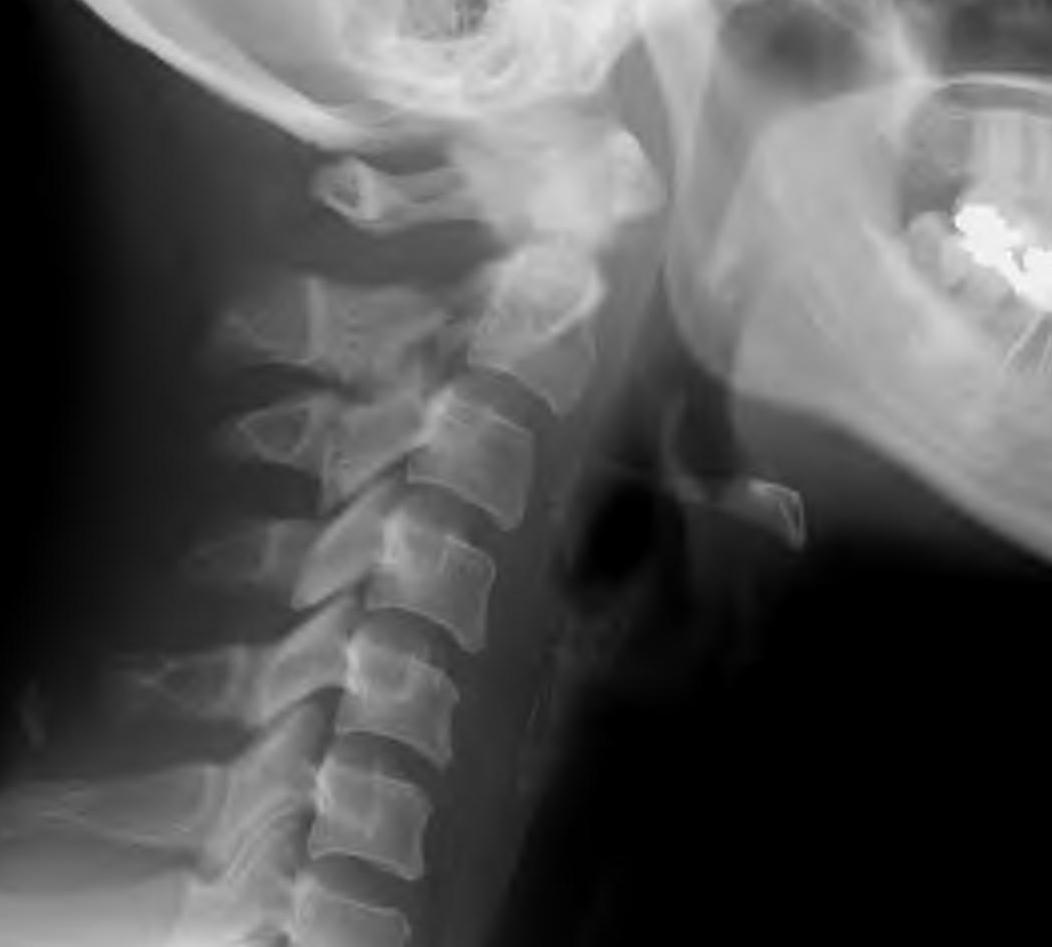

Xray

CT scan